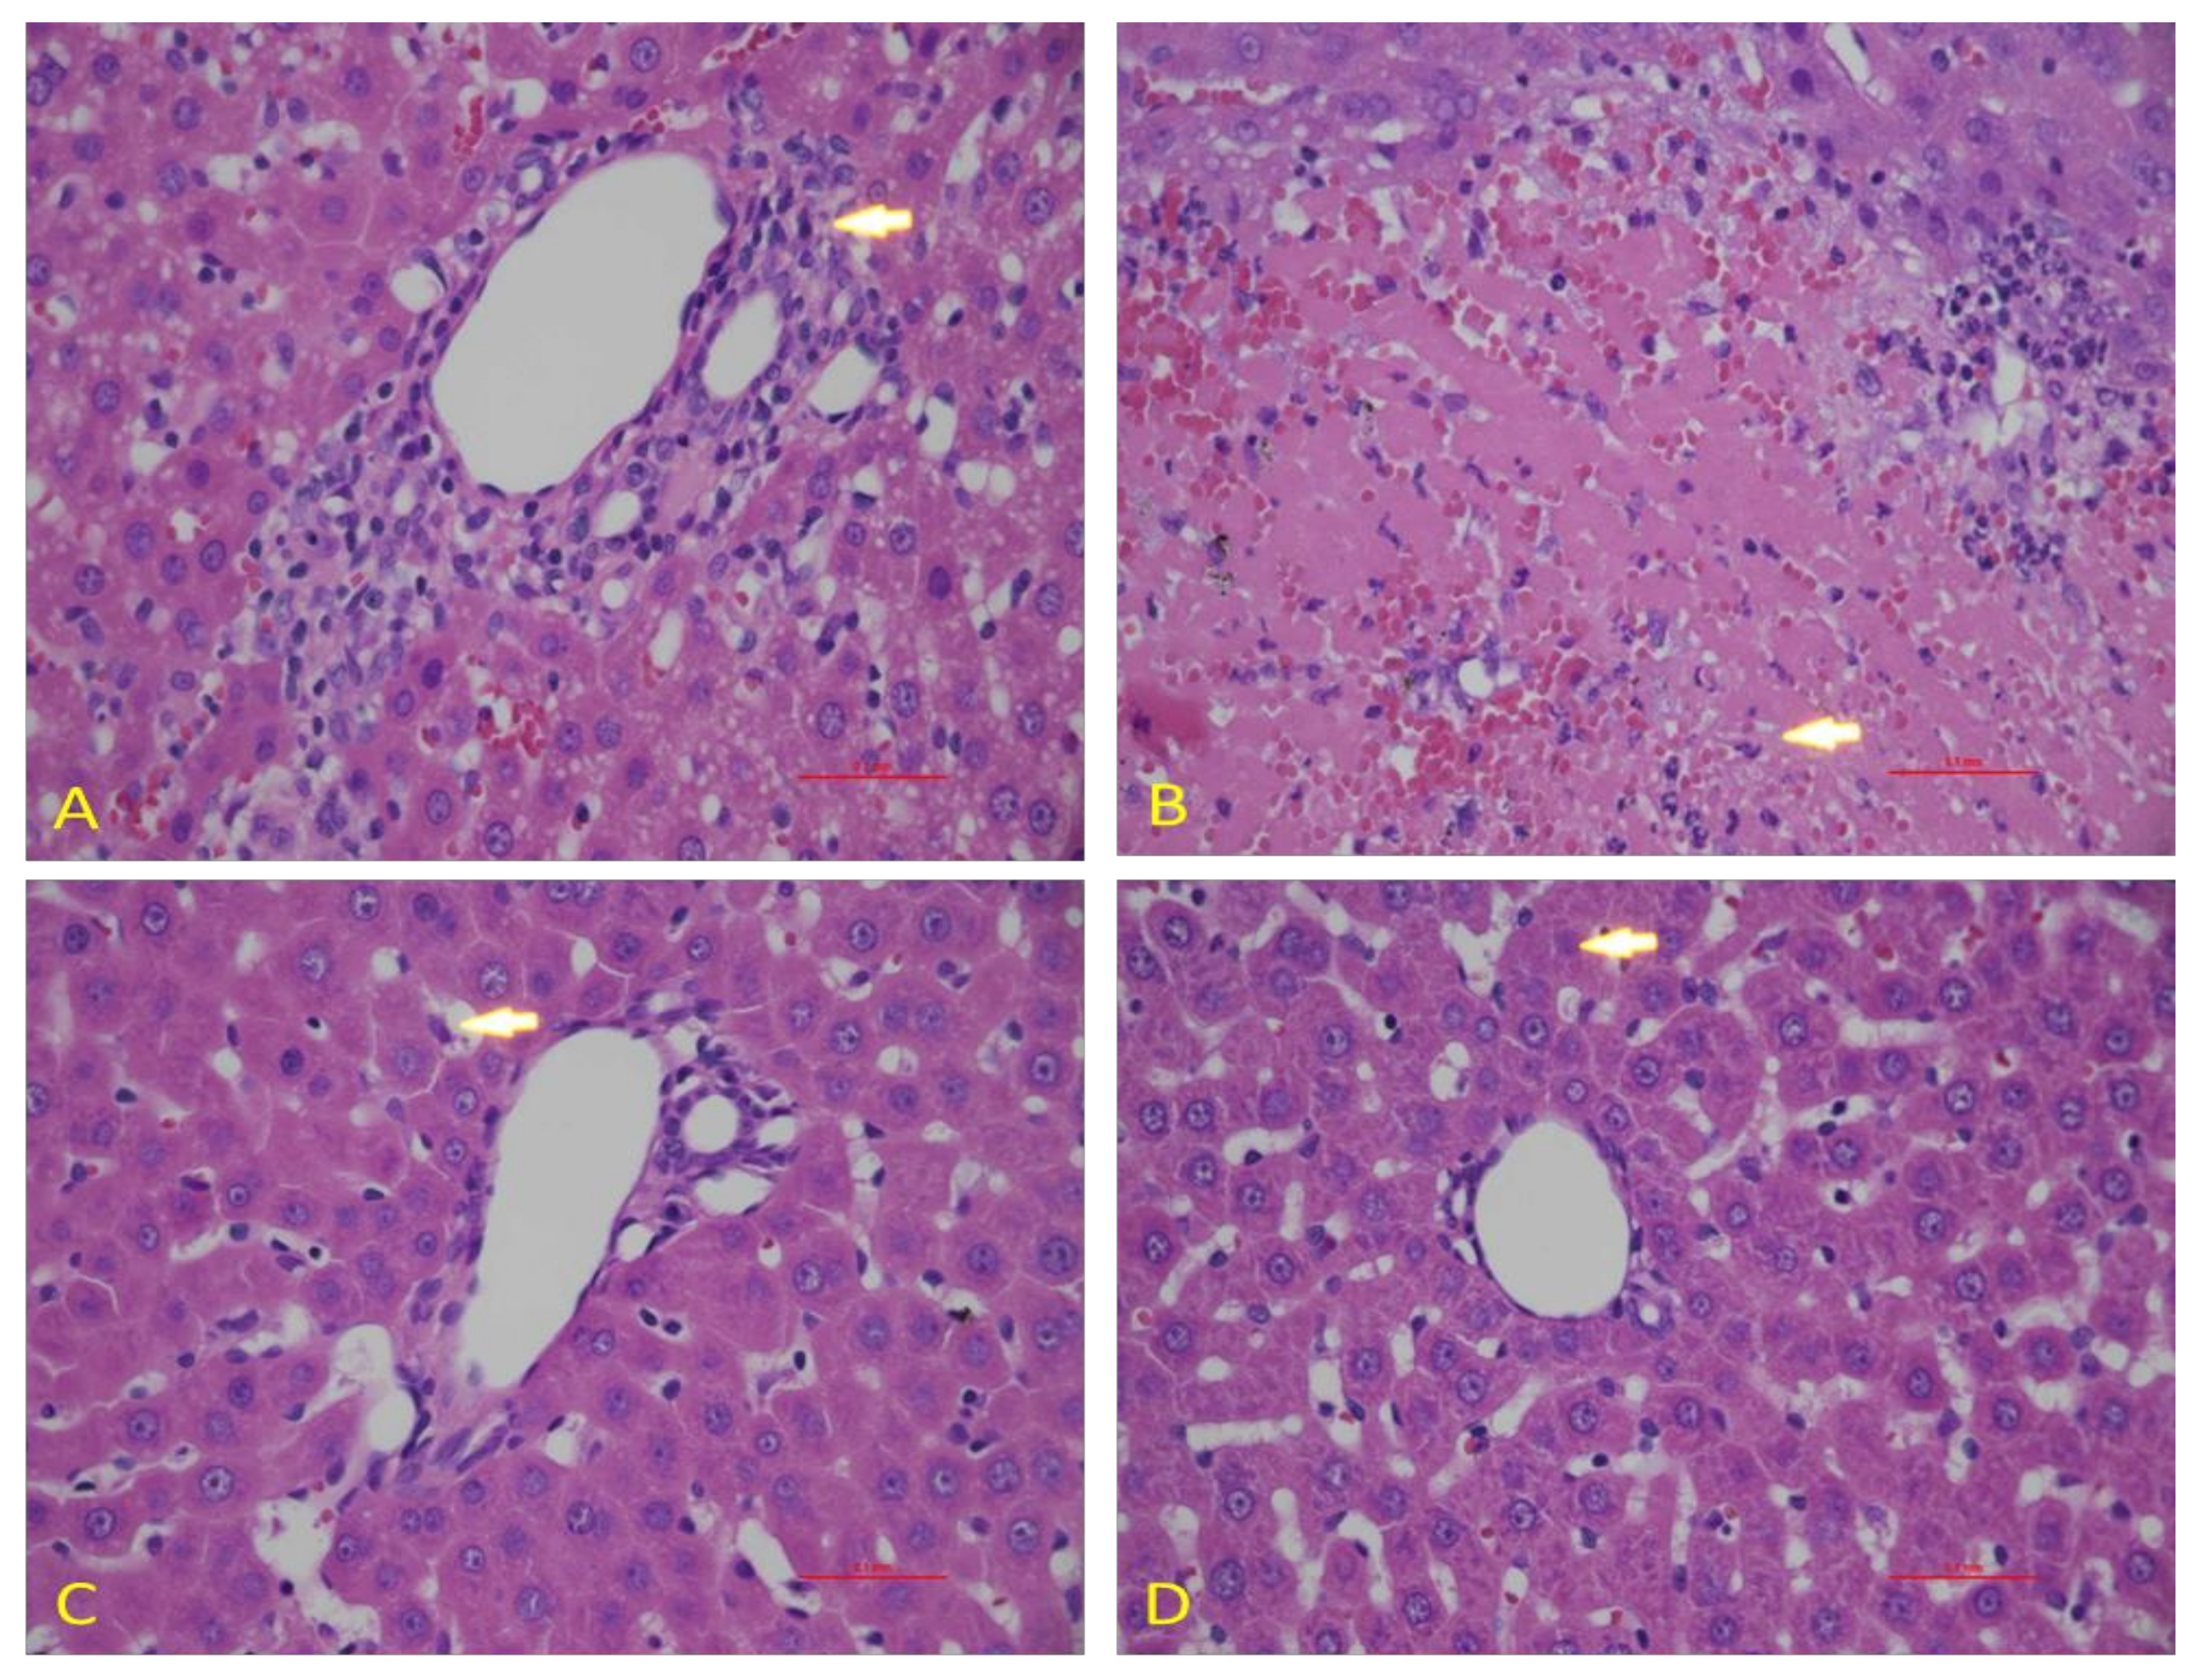

3.5. Effect of Diosmin against DOX-Induced Hepatic Histological Alterations

To confirm the data obtained in our biochemical studies, we evaluated the histological architecture of hepatic tissues after exposure to DOX. We observed a normal hepatic architecture in control animals (Figure 7A). However, DOX exposure caused significant damage in hepatic cells, as shown by the induction of hepatocytes necrosis with marked neutrophilic infiltration (Figure 7B). Nevertheless, diosmin pretreatment showed the presence of a control vein with surrounding normal hepatocytes. However, few residual necrotic hepatocytes were observed in a dose-dependent manner (Figure 7C,D).

Figure 7.

Effects of diosmin pretreatment on light micrographs of the H & E stain liver tissues of 0.1 mm. (A) The normal tissue of the liver. (B) Irregular architecture of liver tissues caused by Dox administration appeared, as indicated by arrows. (C,D) Diosmin pre-treatment reduced harmful effects of Dox in cytoplasmic vacuoles, necrotic hepatocytes, and vascular congestion at both doses.

DOX treatment inhibited PI3K/AKT pathway, as reported in previous findings []. Indeed, the stimulatory action of the PI3K/AKT pathway is crucial for oxidation-mediated cell resistance and apoptosis []. Our results demonstrated the link between the activated form of p-AKT and Bcl-2 up-regulation and subsequently downregulation of Bax expression. A previous study supported the action of p38 mitogen-activated protein kinase (MAPK) in DOX-induced toxicity []. p38 MAPK is a member of the MAPK superfamily composed of four different isoforms: p38α, p38β, p38γ, and p38δ. It has been shown that activation of p38 MAPK is implicated in DOX-triggered apoptosis. In this study, we showed that activation of p-p38 MAPK is a potent enhancer of ROS. In the current study, we showed that diosmin may reverse such enhanced levels of ROS against DOX insult, in line with previous work []. NF-κB is a nuclear transcription factor that plays a pivotal role in the pathophysiology of drug-induced hepatotoxicity []. In its inactive stage, it is more capable of making complexes with its inhibitors, IKα and IKβ. Upon activation, IKα or IKβ promotes phosphorylation of IKβ due to an insult or oxidative stress, leading to the release of NF-κB, enabling its translocation into the nucleus. Our results demonstrated significant activation of NF-κB in response to DOX administration, in accordance with previous findings []. Diosmin pretreatment, however, significantly inhibited the NF-κB- p65 activation cascade. These findings are also consistent with previous reports supporting the capability of a natural compound to hinder NF-κB activation []. Inflammation is a key player in the Dox-induced hepatotoxicity []. In the current study, we examined the genes involved in inflammation, such as TNF-α, IL-1β, IL-6, and iNOS. We found that Dox treatment showed upregulated expression of these genes. Nevertheless, these alterations in gene expression of TNF-α, IL-1β, IL-6, and iNOS were mitigated by diosmin treatment in a dose-dependent manner. These findings were in accordance with previously reported studies [,]. Furthermore, histological evaluation observed in DOX-treated rats revealed marked alterations in liver tissues, such as extensive hepatocytes necrosis with marked neutrophilic infiltration []. Alternatively, pretreatment with diosmin attenuated hepatic necrosis, neutrophilic infiltration, and other dysfunctions, in line with the previously published report [].